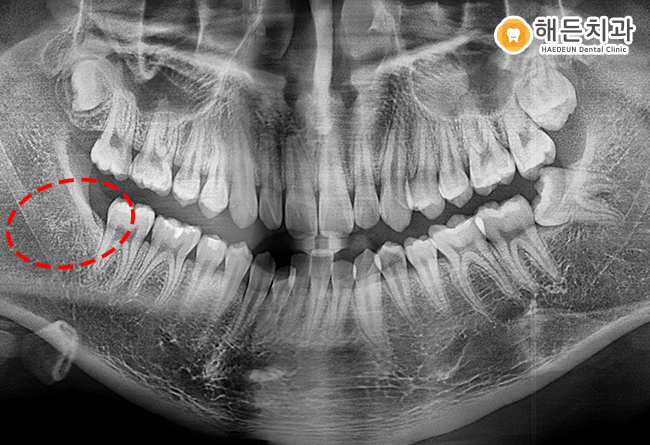

실제로 아산배방치과의 구강 사진에서도

인접 치아와 맞닿는 부위에 변화가

의심되는 부분이 관찰되었습니다.

이러한 상태를 고려해 추가적인 진행을

방지하기 위한 방향으로 아산배방치과에서

발치를 포함한 처치가 논의되었으며,

검진 결과를 바탕으로 치료 계획을 안내드렸습니다.